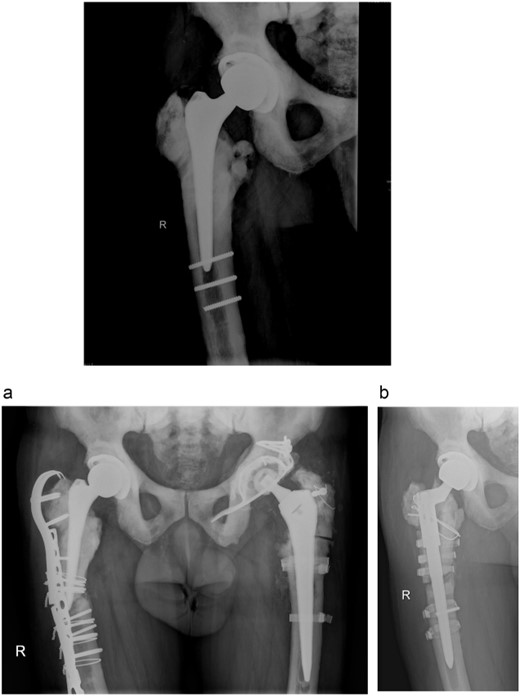

A 73-year-old man showed himself to our hospital in 1989, complaining of left hip pain. X-ray imaging revealed advanced osteoarthritis of the left hip as well as skeletal abnormalities pathognomonic for osteopetrosis. Following earlier intertrochanteric osteotomies carried out elsewhere, there was osteosynthetic material present in the right femur. A cementless isoelastic total hip arthroplasty (THA) was performed (Fig. 1). The greater trochanter was fractured and repaired with screws and cerclages.

Isoelastic uncemented hip arthroplasty. Broken trochanteric part was fixed with cerclage wires and screws.